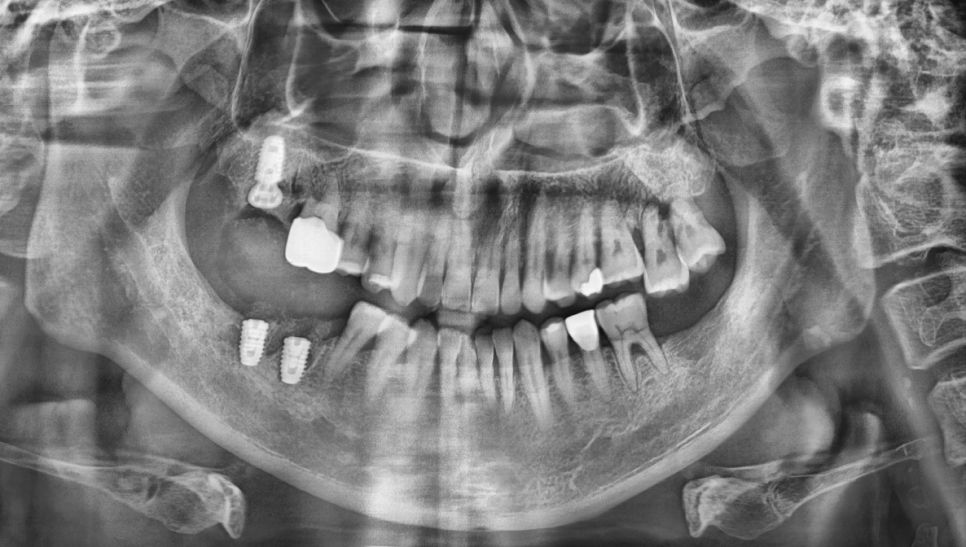

수술하기 전 사진입니다.

사진으로 봐도 오른쪽 윗니, 오른쪽 아래 어금니가 뿌리 주변이 많이 녹아있네요. 환자분은 오른 위 어금니 통증으로 내원하셨습니다.

다행히 골질이 좋아서, 발치 후 즉시 임플란트 식립을 진행했습니다.

식립 이후 임플란트가 잘 유지되어서, 이후 보철물 잘 올리고 마무리했습니다. 환자분이 지금까지 너무 잘 쓰고 계시다고 하네요 :)